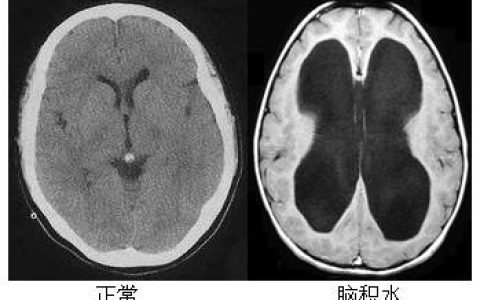

患者女,73岁,因左侧腰痛2天就诊。体格检查结果正常。实验室检测是明显的血小板计数为652000 /立方毫米(参考范围,150000年至400000年),一个正常的完整的血细胞计数。既往无血小板计数。静脉注射造影剂的腹部计算机断层扫描显示左肾动脉充盈缺损,左肾皮质灌注缺损,与左肾动脉闭塞性血栓形成和相关肾梗死相符。进一步检查未发现心源性栓塞性疾病、肾动脉损伤或遗传性血栓形成倾向的证据。基因变异检测呈阳性。下面哪个变量是最有可能与上述结果?

由于血小板计数持续升高,我们对JAK2 V617F变异进行了基因检测,结果为阳性。诊断为原发性血小板增多症。原发性血小板增多症可并发动脉或静脉血栓形成。此类患者的治疗目标是预防血管事件。开始羟基脲和阿司匹林治疗。2个月后随访,患者感觉良好,血小板计数正常。